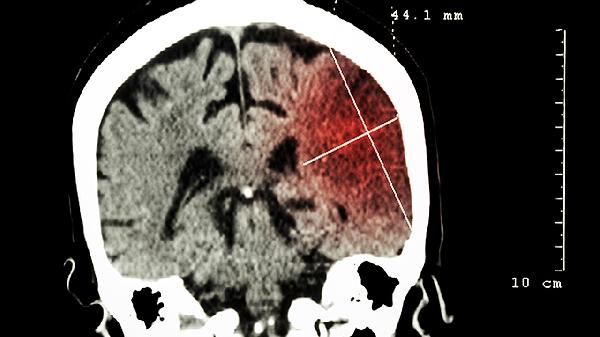

对于青少年脑供血不足的日常护理,建议每天保证7到9小时的睡眠时间,学习过程中每个小时起身活动5分钟,促进血液循环。饮食方面应多吃鱼类、坚果等富含不饱和脂肪酸的食物,少吃高盐高糖的食品。每天坚持30分钟的有氧运动,如慢跑或游泳,避免长时间低头或快速转动头部的动作。如果症状反复出现,或伴随呕吐、意识不清等情况,应及时带孩子去神经内科做进一步检查,比如头颅CT或MRI,排除器质性问题。冬季注意颈部保暖,洗澡水温不宜过高,以免血管过度扩张加重头晕感。